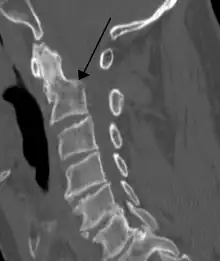

![]() | |

A fracture of the base of the dens (a part of C2) as seen on CT. | |